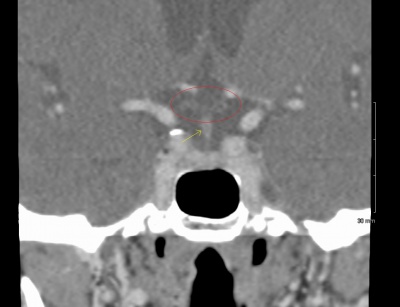

71 year old man with ~10 diopters of myopia OU and tilted optic nerves on clinical exam. Goldmann visual field testing shows bilateral superotemporal defects. CT sella shows no chiasmal lesion.